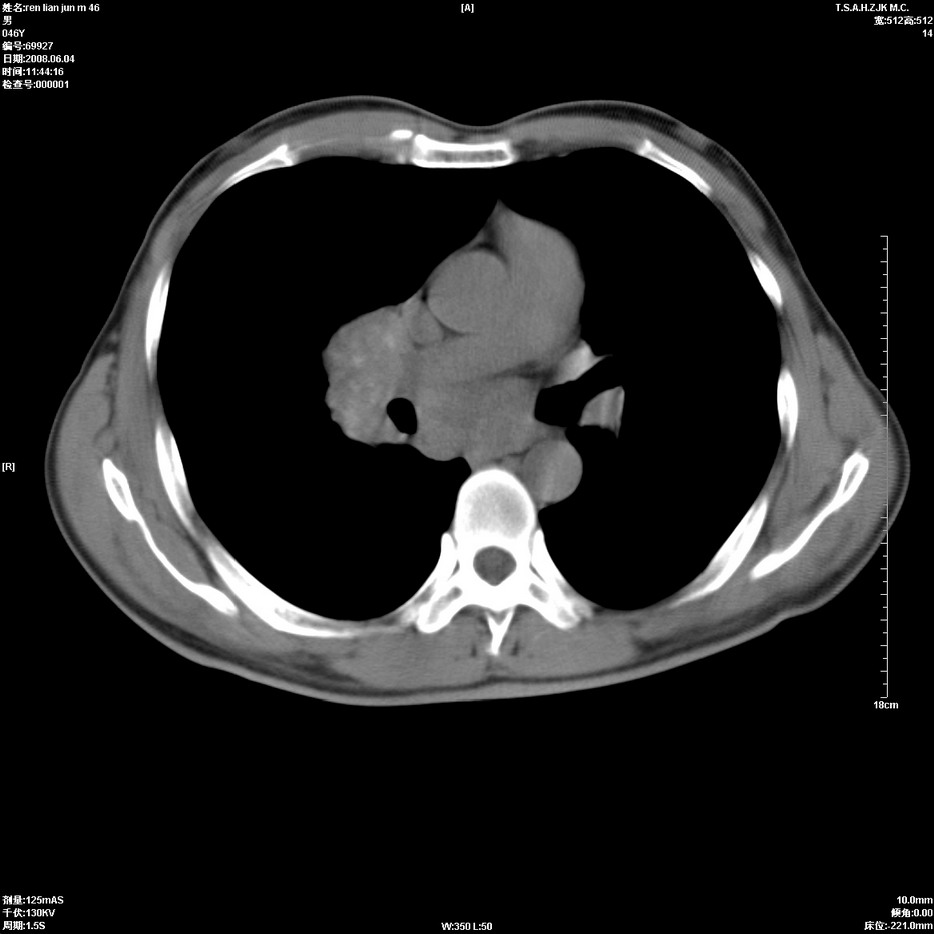

以下是引用qiu999在2008-6-5 17:14:00的发言:[br]考虑右肺中心型肺癌.颅内应做增强检查.

以下是引用形影不离在2008-6-5 19:18:00的发言:[br]右肺中心型肺癌并纵隔及左侧腋窝淋巴结转移,颅内应做增强检查。

以下是引用杀毒软件在2008-6-5 18:33:00的发言:[br]支持考虑右肺中心型肺癌,颅内病变是不是转移,不好说